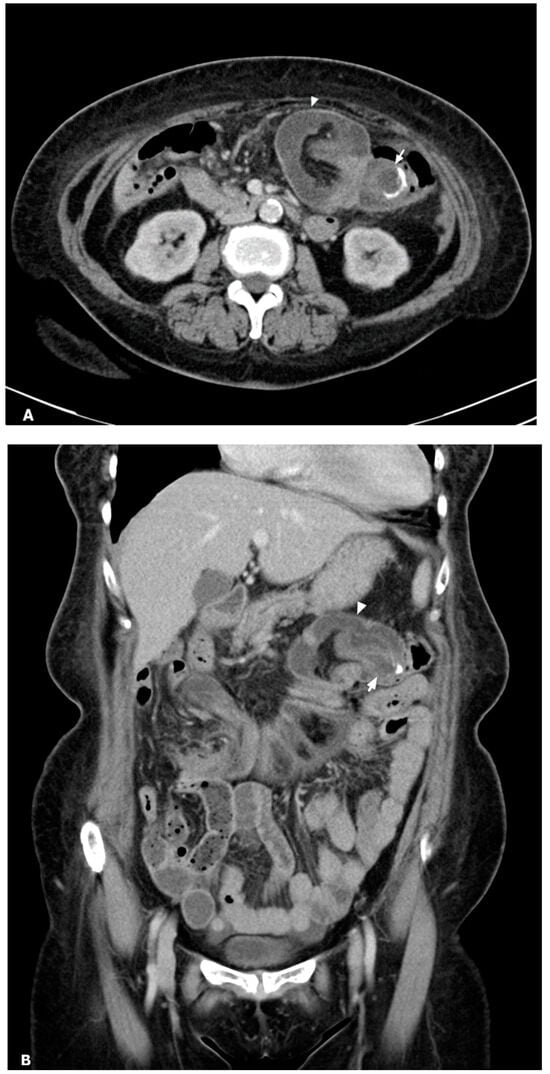

Figure 1.

Contrast-enhanced CT axial (A) and coronal (B) reformatted images: a cystic dilated appendiceal base with mural calcification (arrow) as a lead point causing invagination of the terminal ileum, cecum, and mesentery into the transverse colon (arrowhead). An appendiceal mucocele leading to ileocecal intussusception was found.

A 66-year-old woman with type 2 diabetes mellitus and hypertension presented to the emergency department with intermittent epigastralgia for several days. She denied fever, nausea, vomiting, diarrhea, constipation, black or bloody stool, and back pain. Her prior surgical, social, trauma, and family history were unremarkable. Physical examination showed epigastric tenderness, no obvious palpable mass, and no peritoneal sign. Laboratory data revealed no leukocytosis (9890/μL), no elevation of C-reactive protein (0.444 mg/dL), and mild anemia (hemoglobin: 10.8 g/dL). A bedside echo showed a suspected mass in the central abdomen. Contrast-enhanced abdominal CT revealed invagination of the terminal ileum, cecum, and mesentery into the transverse colon, causing mechanical ileus (Figure 1). A tubular, rim-enhancing cystic lesion with mural calcification was inside the intussusception. Ileocolic intussusception due to an appendiceal mucocele was considered. There was no decreased bowel mural enhancement, no strangulation, and no perforation. No ascites and no peritoneal deposits were present. Exploratory laparotomy showed a 3 cm sized swelling protruding lesion at the appendiceal base inducing intussusception until distal transverse colon (Figure 2). No evidence of peritoneal implants was present. Slow manual reduction of intussusception and an emergent right hemicolectomy with side-to-side anastomosis were performed (Figure 3).